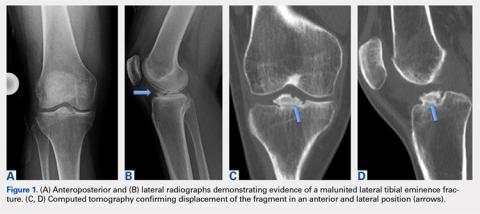

Physical examination revealed significantly reduced knee flexion and extension (+15°-120° on the affected side compared with 5° of hyperextension to 130° flexion of the contralateral knee). Ligamentous examination demonstrated no laxity with varus or valgus stress at 0° to 30° of flexion, negative posterior drawer, and a Grade 2 Lachman and positive pivot shift. She also exhibited pain with attempted right knee terminal extension. Radiographs and computed tomography scans were obtained and reviewed. They revealed a malunited tibial eminence fracture (Figures 1A-1D).

The fragment was located anterior and lateral to its native location, which created a mechanical block during knee motion. Additionally, MRI demonstrated that the anterior horn of the lateral meniscus was displaced and attached to the malunited fragment (Figures 2A, 2B) as well as to nonfunctional ACL fibers. On the basis of the mechanical block restricting extension and the displaced anterior horn of the lateral meniscus compromising meniscal function, we recommended arthroscopic surgery. After discussion of the risks and benefits of the procedure with the patient, she provided informed consent, and it was decided that the patient would undergo arthroscopic fragment excision followed by anatomic repair of the anterior root of the lateral meniscus, and that we would proceed with ACL reconstruction in the future given her subjective instability and physical examination findings of ACL insufficiency.Arthroscopic assessment of the right knee demonstrated the large osseous fragment located in the anterolateral aspect of the joint with the displaced anterior horn of the lateral meniscus attached as well as significant anterior impingement limiting knee extension. Probing of the anterolateral meniscal root in the lateral compartment showed abundant surrounding scar tissue with an abnormal attachment, representing a chronic root avulsion. A mechanical shaver was used to débride the scar tissue and expose the malunited fragment, followed by complete osseous fragment excision with a high-speed burr (Figure 3).